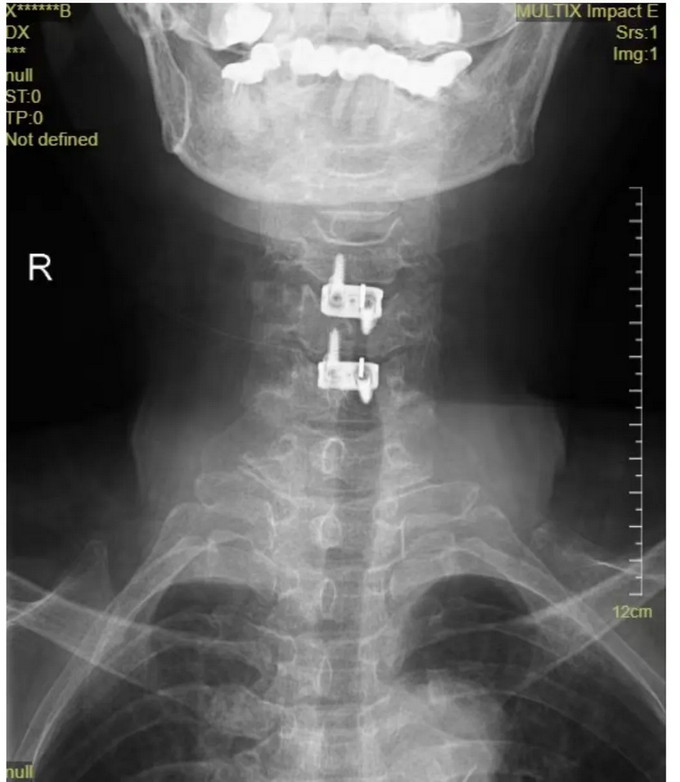

頸椎正位DR

頸椎側(cè)位DR